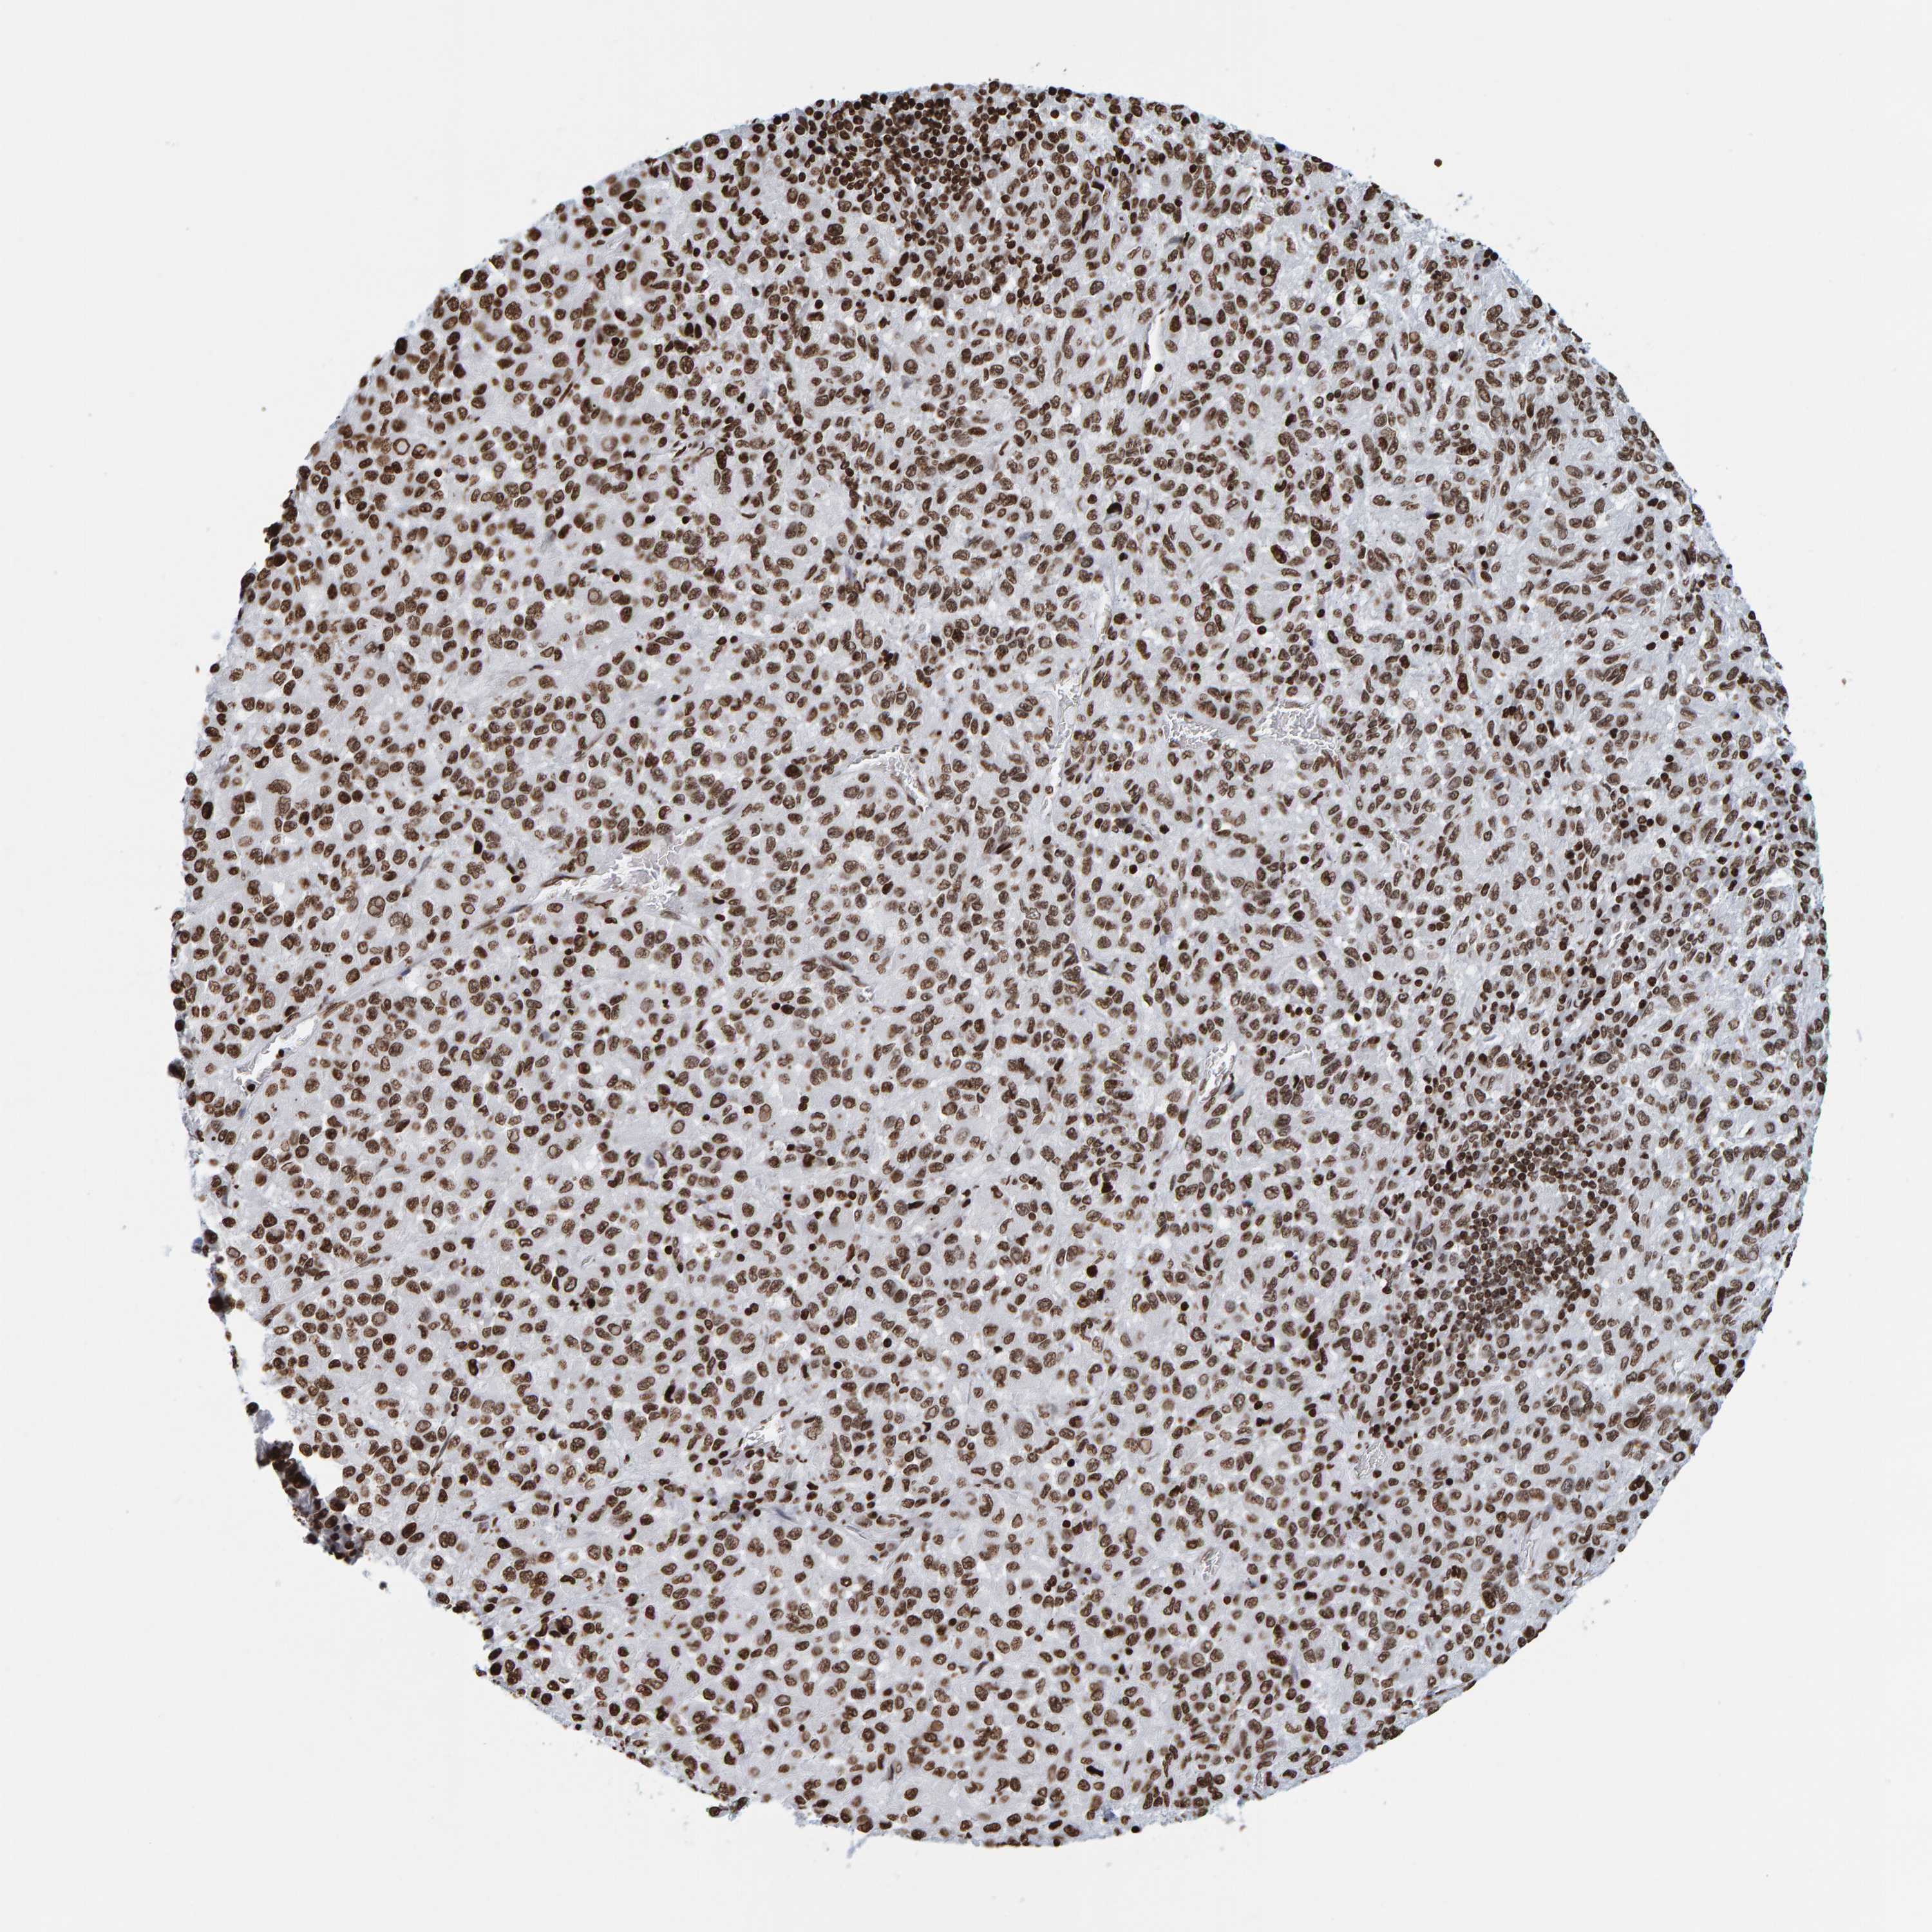

SKIN CANCER - Protein expressioni

A mouse-over function shows sample information and annotation data. Click on an image to view it in a full screen mode. Samples can be filtered based on level of antibody staining by selecting one or several of the following categories: high, medium, low and not detected. The assay and annotation is described here.

Each image is clickable and will lead to virtual microscopy that enables deeper exploration of all samples and also displays staining intensity scores, fraction scores and subcellular localization as well as patient and tissue information for each sample.

Antibody CAB019269

Squamous cell carcinoma, NOS

Squamous cell carcinoma, metastatic, NOS

Squamous cell carcinoma in situ, NOS